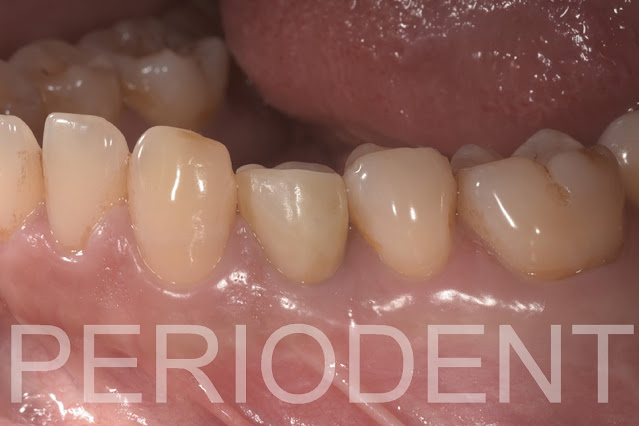

20. 裝上正式假牙後